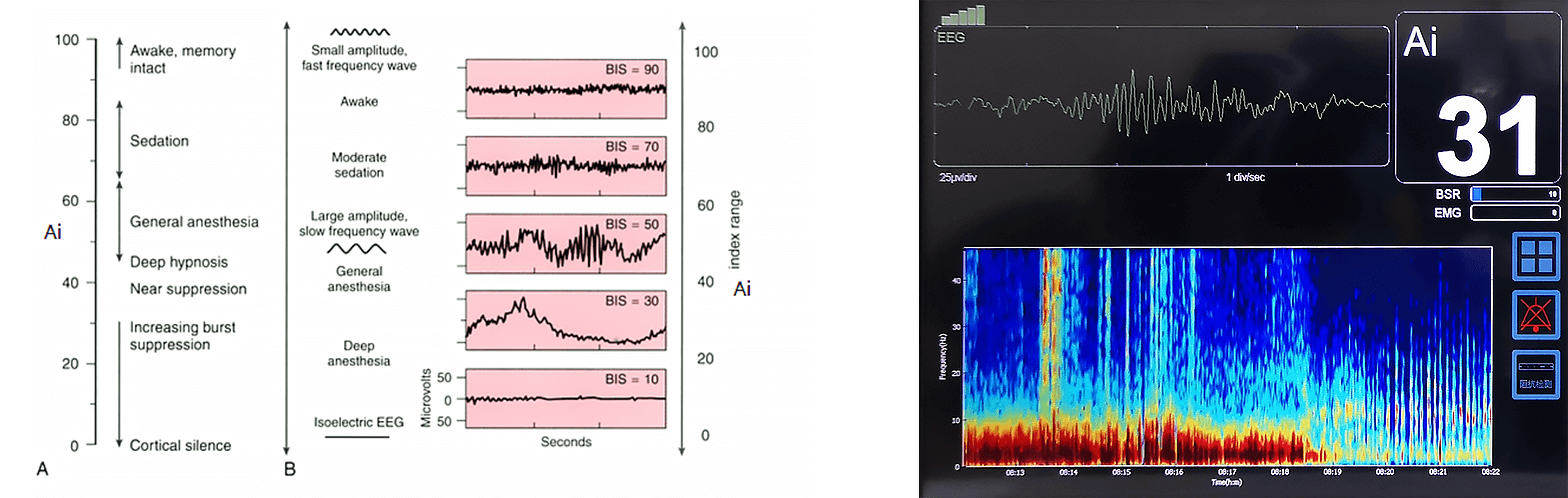

El índice de profundidad de la anestesia Ai utiliza el análisis de señales EEG para cuantificar con precisión la profundidad de la anestesia. Las señales del EEG muestran patrones diferentes a medida que el paciente pasa de la vigilia a la anestesia profunda, incluyendo una actividad aumentada de la onda delta, una inhibición repentina y un estado isoeléctrico final.

Principios básicosAi calcula índices numéricos analizando las características del EEG a través de múltiples dimensiones: dominio de frecuencia, análisis bispectral, dinámica de dominio de tiempo y complejidad de señal. Los modelos estadísticos multivariados asignan estos cambios a un índice continuo que proporciona una evaluación confiable y en tiempo real de la profundidad de la anestesia.

Índice multivariado derivado de las medidas de frecuencia, dominio del tiempo y complejidad de la señal EEG para cuantificar la conciencia desde la vigilia (100) hasta la completa inhibición (0). Umbrales críticos: 100 = vigilia, 70 = sedación leve, 60 = anestesia general, 40 = hipnosis profunda, 0 = EEG isocomputacional (sin actividad cerebral).

Ai (Índice de Conciencia Anestésica)Índice multivariado derivado de las medidas de frecuencia, dominio del tiempo y complejidad de la señal EEG para cuantificar la conciencia desde la vigilia (100) hasta la completa inhibición (0). Umbrales críticos: 100 = vigilia, 70 = sedación leve, 60 = anestesia general, 40 = hipnosis profunda, 0 = EEG isocomputacional (sin actividad cerebral).

Base de datos clínicamente validada robusta

Los algoritmos de inteligencia artificial han sido ampliamente validados a través de numerosos ensayos clínicos y comparados con sistemas internacionales líderes como BIS y Narcotrend. Estos estudios muestran que la Ai muestra una fuerte relevancia clínica, alta consistencia y confiabilidad en la evaluación de la profundidad de la anestesia. El análisis estadístico confirmó una fuerte correlación entre los índices Ai y BIS, proporcionando un fuerte apoyo para su aplicación clínica.